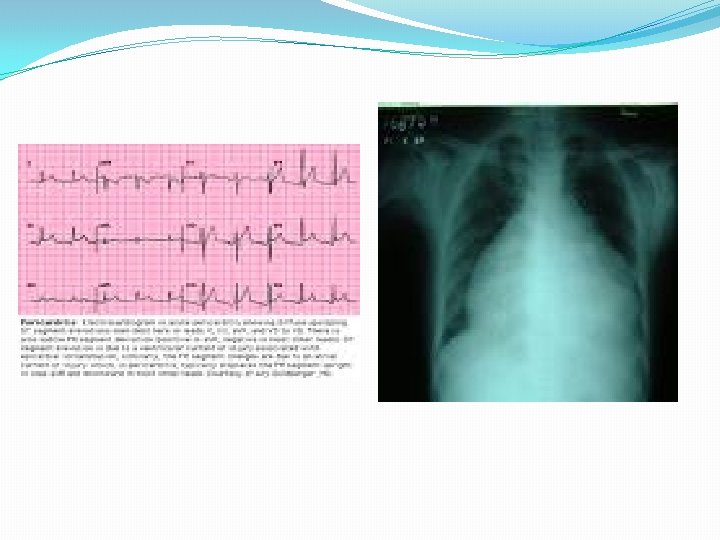

Diagnosis �WBCs, ESR, Troponine and CK-MB usually elevated �ECG (nonspecific ST-T changes and conduction delays are common) �Blood cultures � Viral serology and other specific test for Lyme disease, diphtheria and Chagas disease may be indicated on a case by case basis. �Chest X-rays : show cardiomegaly �Radiology : MRI and Echocardiogram �Heart muscle biopsy

Diagnosis �ECG will show ST elevation, PR depression and T-wave inversion may occur later. �Blood culture �Leukocytosis and an elevated ESR are typical �Other routine testing : urea and creatinine. �Tuberculin skin test is usually positive in tuberculous pericarditis. �Chest x-ray may show enlarged cardiac shadow or calcified pericardium and CT scan show pericardial thickening >5 mm. �Pericardial fluid or pericardial biopsy specimens for fungi, antinuclear antibody tests and Histoplasmosis complement fixation indicated in endemic area.